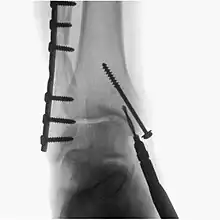

Surgical fluoroscopy

Fluoroscopy is used in various types of surgical procedure, such as orthopaedic surgery and podiatric surgery. In both of those, it is used to guide fracture reduction and in use in certain procedures that have extensive hardware. Specifically, once the fracture is realigned, a surgeon will (with the assistance of their surgical technologist) drill a guide pin into the bone tissue and use flouroscopy to insure proper angle of the pin - then a cannulated drill bit is inserted over the pin to prepare a ‘hole’ for a bone screw. If the surgeon prefers a different angle, they simply reverse the pin and redrill. Flouroscopy will be use for each screw placed -which has greatly improved proper fracture heal due to more accurate reduction.[5]